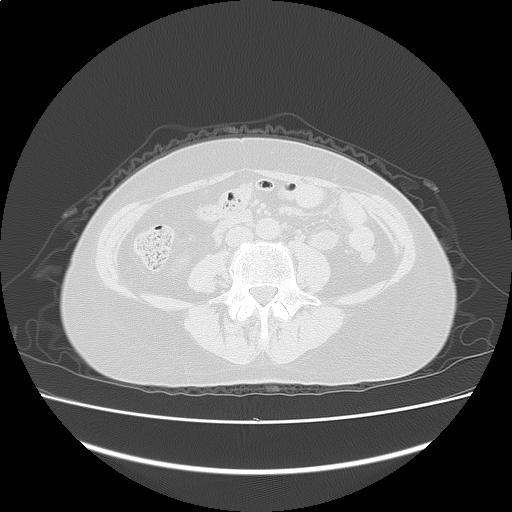

【読影指南】症例画像5

前回のCTにて上行大動脈軽度拡張(41mm)の指摘あり。

年齢: 66歳

性別: 女性

検査部位: 胸腹部

検査種別: CT

CTスライス画像

CTスライス1